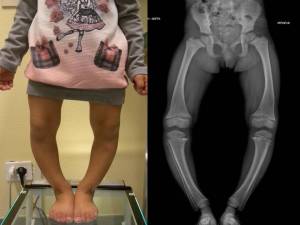

Nei soggetti pesanti che camminano precocemente tale varismo può essere piuttosto accentuato e fonte di preoccupazione per l’ambiente familiare, anche se ad evoluzione spontaneamente favorevole in uno o due anni. Altra forma di varismo da considerare è quella detta anche varismo da mal rotazione (fig 4).

Fig. 4: varismo da malrotazione

Si tratta di pazienti portati a consultazione in genere fra i 6 e i 12 anni, che presentano un difetto di torsione degli arti inferiori quasi sempre associato ad esagerata antiversione del collo femorale. Quando vengono osservati di fronte, con il bordo interno dei piedi accostato, le rotule guardano all’interno – “strabismo rotuleo convergente”, le ginocchia sembrano vare e la testa del perone sporge più del normale. Se il bambino viene posto con le rotule frontali, le punte dei piedi divergono ed il varismo, se apparente svanirà del tutto, o si attenuerà solo in parte (fig 4). In questi casi, per una corretta valutazione, è opportuno eseguire delle radiografie panoramiche degli arti inferiori in ortostasi, sia con i piedi accostati (rotule convergenti) sia con i piedi extra ruotati di circa 30° (rotule frontali), in modo da misurare l’asse meccanico e poter capire se vi sono indicazioni chirurgiche.